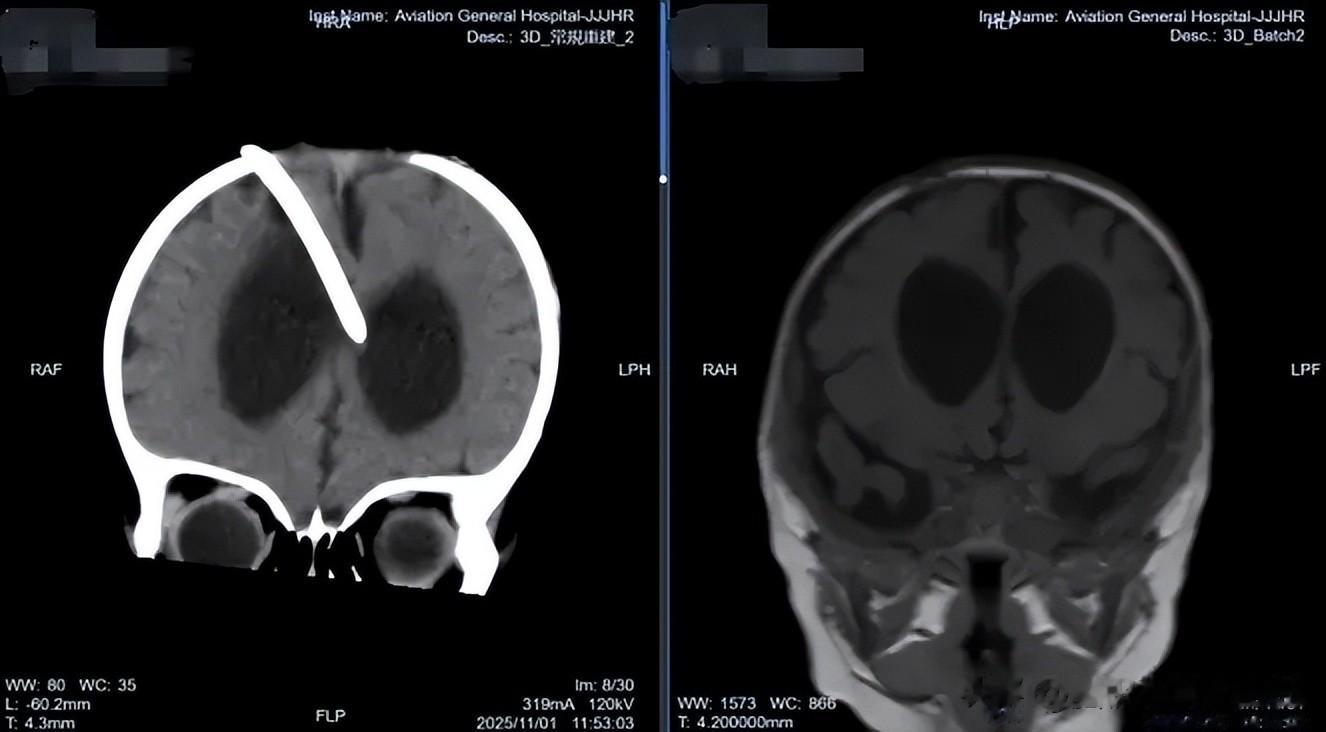

面对患儿的复杂情况,肖庆主任没有急于制定手术方案,而是凭借丰富的临床经验,首先深入了解孩子的全面健康状况,初诊断考虑颅内脑脊液异常,明确的颅内感染证据是治疗的关键。

随后于 2025 年 11 月 6 日在全麻下为患儿实施了神经内镜下第三脑室底造瘘术 + 原分流管去除术。术中留取原分流管管头培养,回报表皮葡萄球菌(+),这一发现证实了术前的感染判断,也解释了为何初次分流术后患儿症状未见改善。